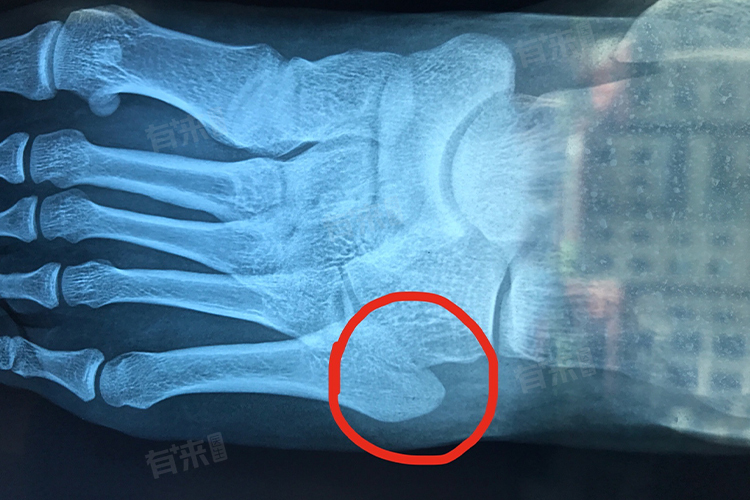

第五跖骨基底部骨折常因足部扭伤等外力作用引起,表现为局部疼痛、肿胀、压痛,行走困难,给患者生活带来诸多不便,应对方法主要包括制动休息、冰敷消肿等。

日常生活中应注意选择合适的鞋子,在骨折愈合初期,穿宽松、柔软、有良好支撑的鞋子,避免对受伤部位造成挤压,注意观察足部肿胀、疼痛及皮肤颜色变化,如有异常及时处理。定期复查X光,了解骨折愈合情况,遵循医生的康复指导,逐步恢复正常活动,避免过早负重或剧烈运动,防止骨折再次移位,确保骨折顺利愈合。